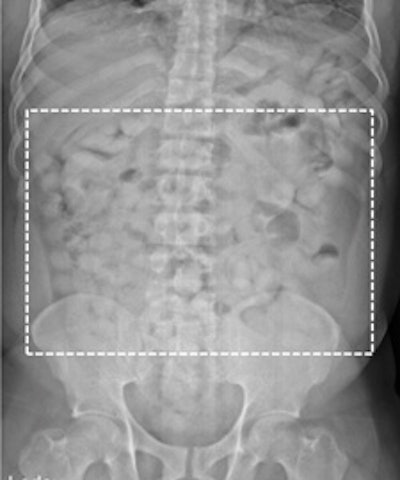

Top left: Low-dose linear slit digital radiography (LSDR) of a typical body packer with 145 intracorporal packs along the alimentary tract. Bottom left: Magnified view of the packs. Note the radiolucent rim within the periphery of the packs due to air trapping creating the so-called "double-condom sign" and "halo sign." Top right: DR of a typical body packer with 83 cocaine packs in the gastrointestinal tract. Bottom right: Note the longitudinal packs (weight approximately 10 to 12 g) projecting over the colon. The magnified view depicts the typical "double-condom sign" due to inevitable air trapped within the wrapping layers during manufacture.DR and low-dose linear slit digital radiography exams were less accurate. CT exams had an overall accuracy rate of 97.1%, followed by DR (71.4%, and 60% for low-dose linear slit digital radiography).

Left: LSDR of a typical body packer with a multitude of cocaine packs within the alimentary tract. Right: Same image with highlighted intestinal packs.The authors noted that it was also important for a radiology report to contain a precise description of the number of drug containers that are identified, and to indicate where they are located in the intestinal tract. This makes the job of the feces evaluators easier.